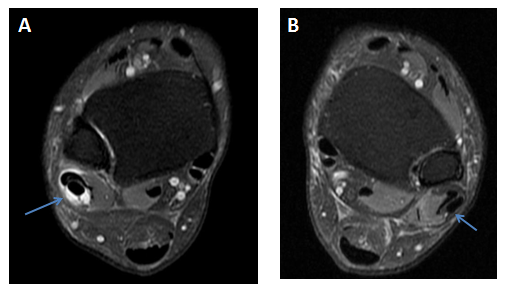

Axial fat saturated proton density MRI image of the right ankle at tibiofibular syndesmosis showed the presence of fluid within the common sheath around the peroneal tendons; it means that the fluid extension was up to the musculotendinous junction. The left side demonstrated no fluid effusion around the peroneal tendons (Figure 5 & 6).

Figure 5 (A) Axial fat saturated proton density MRI image of the right ankle at tibiofibular syndesmosis shows fluid in the common sheath around the peroneal tendons (blue arrow). (B) Left ankle for comparison shows no fluid around the peroneal tendons (blue arrow).

Sagittal fat saturated proton density MRI image of the right ankle displayed a significant amount of fluid extending down along both peroneal tendons till their bone attachments (Figure 6).

Figure 6 (A) Sagittal fat saturated proton density MRI image of the right ankle shows fluid in the common peroneal sheath and around the peroneus longus and breves tendons (blue arrows). (B) Left ankle for comparison shows no fluid around the tendons.

Sagittal and axial fat saturated proton density MRI images of the right ankle revealed fluid effusion in the right subtalar joint (Figures 7A & 7B).

Figure 7 (A) Sagittal, (B) axial fat saturated proton density MRI images of the right ankle showing fluid in the subtalar joint (blue arrow). (C) Axial fat saturated proton density MRI image at a lower level showing fluid around the flexor hallucis longus tendon (white arrow).

Axial fat saturated proton density MRI image of the right ankle confirmed the presence of fluid effusion around the flexor hallucis longus tendon (Figure 7C). Axial proton density MRI image of the right ankle proved intact muscular tendons and ligaments (Figure 8).